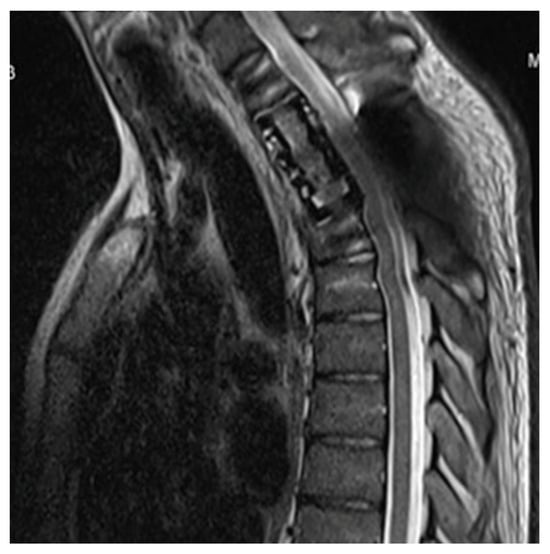

2. Case Report